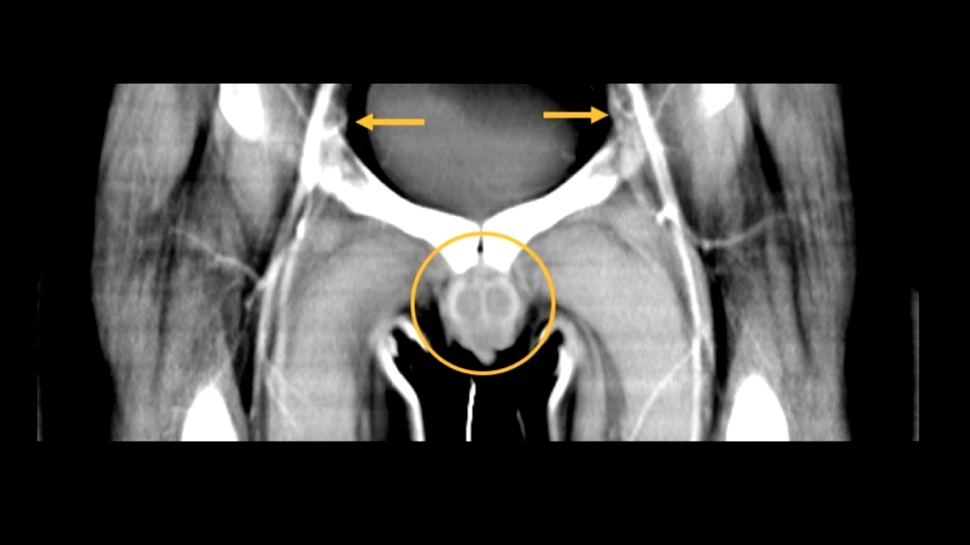

Procedura la care a fost supus bărbatul a fost una îndrăzneaţă, medicii propunându-şi transplantarea penisului, scrotului şi peretelui abdominal inferior, în total fiind transplantată o masă de peste două kilograme.

Operaţia a durat 14 ore şi a fost nevoie de o echipă formată din 11 chirurgi care să conecteze vase de sânge care puteau ajunge şi la o grosime de unu-doi milimetri.

La un an de la efectuarea procedurii, medicii explică faptul că recuperarea pacientului merge bine, masa a stabilit legătura cu nervii organismului pe care a fost transplantată. „Are senzaţie normală la axul şi vârful penisului transplantat şi poate localiza senzaţia de atingere … Pacientul urinează în timp ce stă, fără încordare, frecvenţă sau urgenţă”, au declarat aceştia.